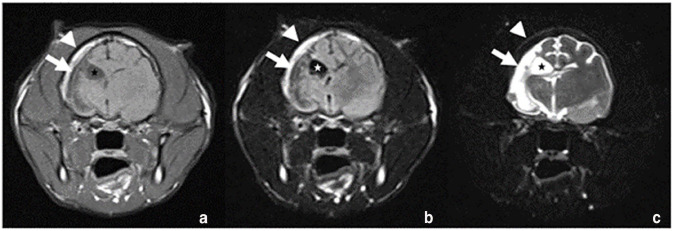

病例摘要:一只 4 岁大的猫咪因急性发作侧向神经性中枢神经系统(CNS)症状和癫痫发作而就诊。血液和血清生化指标均在正常范围内。影像诊断显示右脑 CT 和 MRI 严重异常,类似于人类医学中的戴克-达维多夫-马森综合征(DDMS)。该综合征包括脑半球萎缩、代偿性颅骨骨质增生和脑室肥大。这种变化以前仅在一例年龄相仿的猫科动物身上出现过一次。在人类,DDMS 被描述为胚胎和围产期发育障碍或幼年期获得性损伤:本病例报告表明,在一些罕见的成年猫病例中,如果没有进一步的影像学诊断,先天性疾病可能会被忽视,而这些病例的首次临床症状出现得较晚。

Case summary: A 4-year-old cat was presented with acute onset of lateralised neurological central nervous system (CNS) signs and seizures. Haematological and serum biochemical parameters were within normal limits. Imaging diagnostics revealed severe CT and MRI abnormalities of the right brain, similar to Dyke-Davidoff-Masson syndrome (DDMS) in human medicine. This syndrome includes cerebral hemiatrophy with compensatory calvarial hyperostosis and ventriculomegaly. Such changes have previously been reported only once in a single feline case of approximately the same age. In humans, DDMS is described as an embryonic and perinatal developmental disturbance or an acquired injury in early childhood.